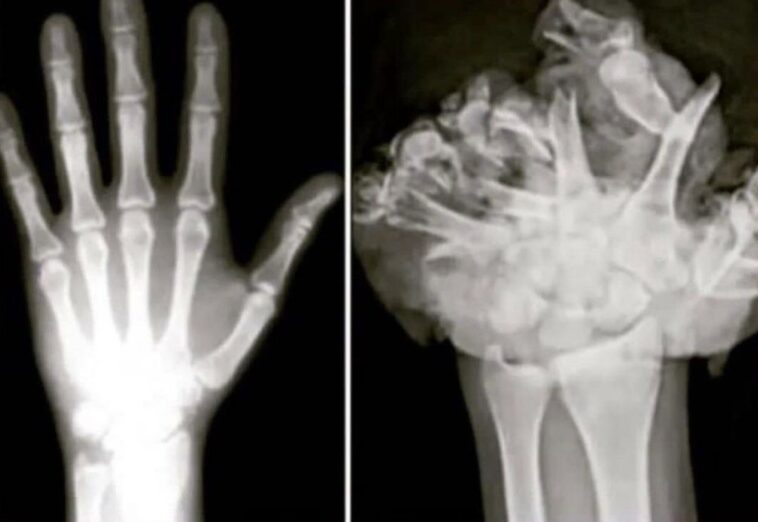

6. Normální ruka / ruka po výbuchu ohňostroje.

Co dodat,… ohňostroje vážně nejsou sranda.

Normální ruka / ruka po výbuchu ohňostroje